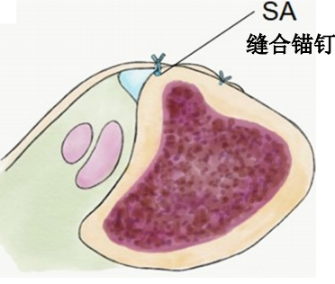

SPR撕脱开放手术锚钉修复

SPR撕脱关节镜手术锚钉修复

通过切除腓骨后方部分骨质,可以加深腓骨沟,改变、并增加了腓骨肌腱的稳定。

内镜下腓骨沟加深手术

大部分急性损伤可以使用直接缝合修复,对慢性损伤则需根据患者的具体病理改变选择,如单纯的支持带结构损伤,可以直接缝合修复。如果直接修复不够稳定,需用其他组织加强。如果腓骨外踝窝较浅时,就需要使用加深手术。